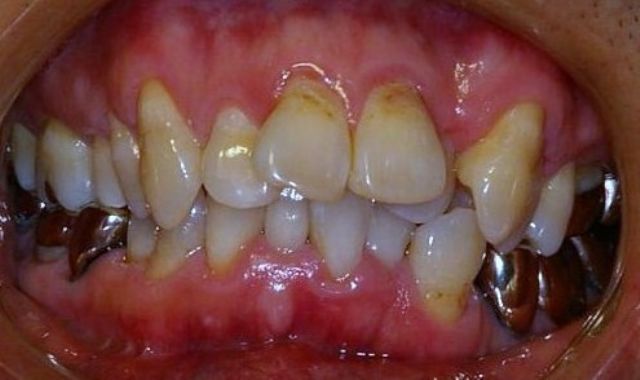

| @上顎前突(矯正用インプラント使用症例) | |||||||||||||||||||||||||||||||||||

かなり重度の上顎前突症例です。 バードフェイス(鳥貌)と言われる横顔で、以前(2000年頃まで)は矯正不可能と言われていた症例ですが 矯正用インプラント(矯正用ビス)を入れることにより、短期間で改善できた例です。 尚、矯正用インプラントは、力がかかる時だけ入れるもので使用後は簡単に外せます。 矯正用インプラントは、2000年頃より日本に導入された治療法です。(詳しくは、コチラ) もちろん、矯正用インプラントを使用しなくても治る症例も沢山あります。 |

上顎の歯槽骨までも後ろに後退させて側貌も改善されています。(顔は伏せています。) 歯並びだけではなく、顔の見た目も改善することが矯正の目標と考えています。 また、歯列もV字型の咬み合わせからU字型になって咬み合わせも良くなり、口元の審美性も改善されています。 |